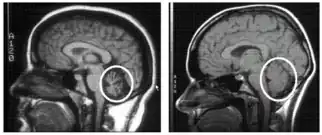

Magnetic resonance imaging scans of two different brains. The scan of the brain on the left indicates a weakened, deteriorated cerebellum of a human with cerebellar degeneration. The scan of the brain on the right indicates a healthy, normally-functioning cerebellum of a human.

To select an appropriate and accurate diagnostic test for cerebellar degeneration, it is crucial that a range of factors specific to each patient are taken into consideration. These include; the patient's age, acuity of their signs and symptoms, associated neurological conditions, and family history of hereditary forms of cerebellar degeneration.[3] A diagnosis for cerebellar degeneration is regarded after any of the aforementioned signs and symptoms surface. For genetically classified forms of cerebellar degeneration, genetic testing can be carried out in order to confirm or deny the diagnosis, where this form of testing is only possible if the gene responsible for the cause of the condition is recognised.[24] In saying this, for most conditions the genetic cause of cerebellar degeneration is unidentified, hence these patients cannot proceed with genetic testing.[1] In cases where cerebellar degeneration is acquired, a diagnosis can be established using imaging methods such as computerised tomography (CT scans) and magnetic resonance imaging (MRI), necessary to detect brain abnormalities in patients with cerebellar degeneration.[25]